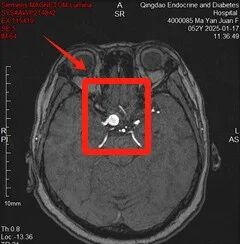

张女士自患糖尿病以来便很注重自身健康,会定期进行查体。最近,我院健康管理中心AI查体系统结合张女士上次检查时间、个人年龄等信息、专项诊疗方案、生活习惯、遗传等多方面因素,为其生成个性差异化的深度体检方案,方案中包含了头颅磁共振动脉成像检查。在检查过程中,医生在她的颅内发现了一个“不定时炸弹”——动脉瘤。这个消息如同一记重锤,让张女士及家人瞬间紧张了起来。但幸运的是,因为发现及时,张女士得以迅速接受专业治疗,解除了“静默威胁”。

三、磁共振:颅内动脉瘤的侦察兵

磁共振(MRI)是一种先进的医学影像技术,它在颅内动脉瘤的诊断中发挥着重要作用。通过磁共振检查,医生可以清晰地观察到脑部动脉的走行区,发现瘤样扩张、结节样的突出,从而确诊动脉瘤与其他检查方法相比,磁共振具有无创、无辐射、分辨率高等优点,能够更准确地评估动脉瘤的大小、形态和位置,为后续的治疗提供重要依据。